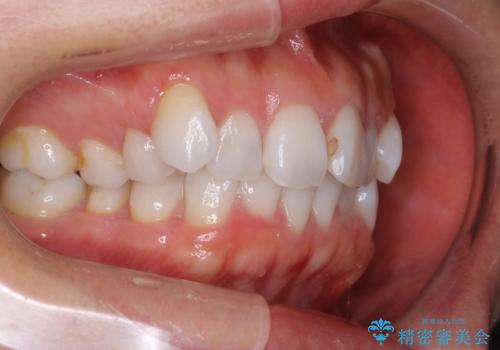

抜歯せずに八重歯のマウスピース矯正

八重歯がシビアな場合、抜歯をしないと治せないケースもありますが、奥歯の位置関係を修正したり、歯のサイズダウンを行うことで、抜歯をせずに改善できる場合もたくさんあります。